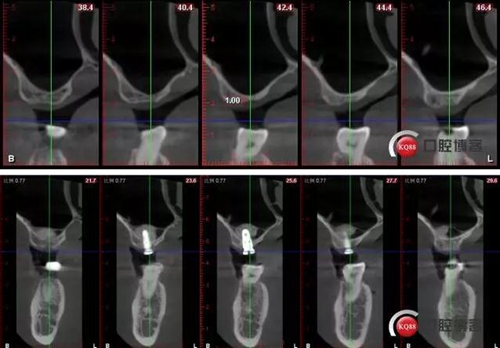

CBCT檢查:

術后CBCT

術前術后CBCT對比: